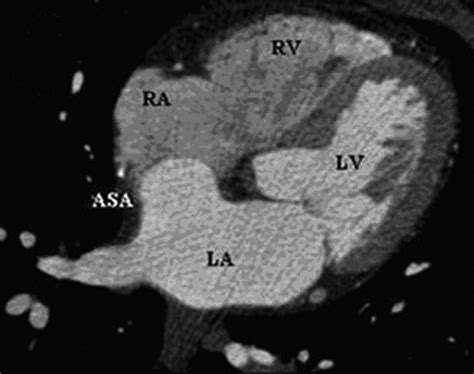

• Cardiac MRI: Magnetic resonance imaging offers high-resolution images of the heart, providing a comprehensive view of the aneurysm and its impact on heart function.